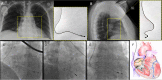

Inadvertent malposition of a pacemaker lead in the left ventricle is uncommon, but it should not be misdiagnosed. We report the case of a 68-year-old woman with symptomatic sick-sinus syndrome requiring pacemaker implantation. Shortly afterwards the lead was extracted and a new pacemaker was contralaterally implanted due to pocket hematoma and suspected lead fracture. Three months later, she was referred to our echocardiography laboratory complaining of asthenia. At transthoracic echocardiography an echo-bright linear structure was recognized in left atrium, passing through the mitral valve and leaning against the posterior left ventricular wall. In short-axis and apical views, the lead apparently crossed the interatrial septum through patent foramen ovale. The QRS-paced electrocardiogram showed right bundle branch block morphology. The lead was apparently well positioned, examining the chest X-ray postero-anterior view. On the contrary, by latero-lateral view and left-anterior oblique view, lead curvature was consistent with misplacement into the left ventricle. Malposition was confirmed by transesophageal echocardiography. Given the relatively recent implant, system revision with lead extraction was scheduled and completed without complications. This case report is intended to improve our awareness in the prevention and in the prompt detection of misplaced pacemaker leads in order to manage an immediate correction. <Learning objective: During lead implantation, fluoroscopic left-anterior oblique view should be always used to ensure correct positioning. At least 3-6 limb leads should be carefully monitored during the procedure, and a 12-lead standard electrocardiogram should be performed shortly afterwards for the paced QRS morphology. Lateral chest X-ray should always be taken after implantation. In cases of doubt, echocardiography (transthoracic or transesophageal) may confirm abnormal lead placement defining the route covered by the catheter.>.